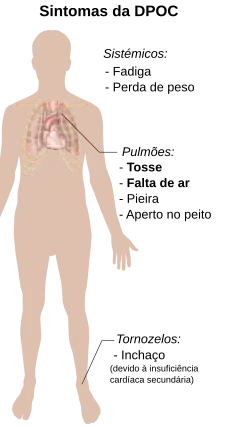

Sinais e sintomas

Os sintomas mais comuns da doença pulmonar obstrutiva crónica são produção de expectoração, falta de ar e tosse produtiva.[17] Estes sintomas manifestam-se durante um longo período de tempo[18] e geralmente vão-se agravando ao longo do tempo.[5] Não é claro se existem ou não diferentes tipos de DPOC.[2] Embora antigamente a doença se dividisse em enfisema e bronquite crónica, hoje considera-se que enfisema é apenas uma descrição das alterações no pulmão, e não uma doença em si, e que a bronquite crónica descreve apenas os sintomas que podem ou não ocorrer no contexto de DPOC.[8]

Falta de ar

A falta de ar é geralmente o sintoma que mais incomoda as pessoas com DPOC.[19] O sintoma é geralmente descrito em termos leigos como "custar a respirar", "sentir-se sem fôlego" ou "não conseguir inspirar ar suficiente".[20] Dependendo do contexto cultural, podem ser usados diversos termos.[17] Geralmente a falta de ar é mais intensa ao realizar esforços de longa duração e vai-se agravando ao longo do tempo.[17] Em estágios avançados da doença, a falta de ar manifesta-se até mesmo em repouso e pode-se manifestar continuamente.[21][22] Em pessoas com a doença, a falta de ar é uma fonte de ansiedade e diminuição da qualidade de vida.[17] Muitas pessoas com DPOC avançada recorrem a respiração freno-labial para aliviar a falta de ar. Esta técnica respiratória consiste em inspirar o ar pelo nariz com a boca fechada e expirar pela boca com os lábios cerrados o máximo possível.[23][24]

Na DPOC a expiração pode ser mais demorada do que a inspiração.[25] Pode ocorrer sensação de aperto no peito,[17] embora não seja comum e possa ser causada por outro problema.[19] Em pessoas com vias aéreas obstruídas é possível ouvir um sibilo durante a auscultação com um estetoscópio.[25] O tórax em tonel é um sinal característico de DPOC, embora seja relativamente pouco comum.[25] À medida que a doença avança, o corpo pode adquirir uma postura com tendência para a posição de tripé.[18]

Os estádios avançados de DPOC podem causar pressão elevada nas artérias do pulmão, o que comprime o ventrículo direito do coração.[5][28][29] Esta situação é denominada cor pulmonale e manifesta-se através de sintomas como pernas inchadas[17] e pressão venosa jugular.[5] A DPOC é a causa pulmonar mais comum de cor pulmonale,[28] embora a sua prevalência tenha diminuído desde que foi introduzida a oxigenoterapia.[18]

A DPOC ocorre muitas vezes em simultâneo com uma série de outras condições, devido em parte aos fatores de risco que partilha com essas doenças.[2] Entre estas condições estão a cardiopatia isquémica, hipertensão arterial, diabetes, osteoporose, cancro do pulmão, perturbações de ansiedade, disfunções sexuais e depressão.[2][30] Em pessoas com doença grave, é comum a sensação de fadiga.[17] O hipocratismo digital não é específico da DPOC e pode indicar a possibilidade de haver um cancro do pulmão.[31]